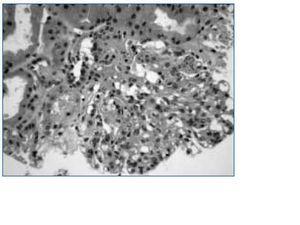

Una semana después ingresa en anasarca y oliguria, encontrando urea 287 y Cr 4,1mg/dl. Ante la presencia de hipoalbuminemia severa se administra albúmina, se sube la dosis de diuréticos pese a lo cual empeora la función renal. En orina se encuentra Na < 10 mEq/l y Cr > 130 mg/dl orientándose el fracaso renal agudo de origen prerrenal. Se retiran los diuréticos pero desarrolla anuria por lo que se coloca catéter venoso y se inicia hemodiálisis. La biopsia renal (fig. 1) muestra 8 glomérulos, con leve esclerosis y colapso capilar en el polo vascular, otros con adherencia capsular o colapso de luces capilares; el intersticio y túbulos sin alteraciones. Inmunofluorescencia: IgM+/- y C3++ con patrón granular mesangial. Con estos hallazgos se diagnostica de glomeruloesclerosis focal y segmentaria (GEFS); se administran tres bolus de esteroides y se continuó con prednisona y ciclofosfamida oral siendo dado de alta, en hemodiálisis periódica, y en anuria.

Figura 1.